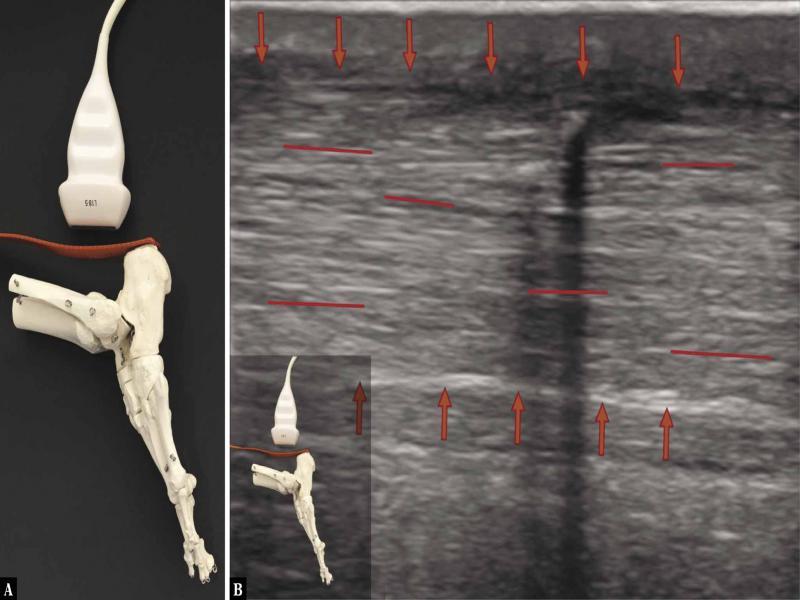

Fig. 6.

![Ultrasound examination protocol. A. The transducer is placed longitudinally above the calcaneal tuberosity, along the AT; active maximum plantar flexion of the ankle joint [curved arrow] with the diagnostician’s hand applying ground-like foot resistance [straight arrow] as in the heel-rise test. No tension is seen in the AT, which is undulated. The heel-rise movement is performed not by the force of the triceps surae muscle, but with the strength of the other plantar flexors. The image indicates a dysfunction of the surgically treated AT, healing with elongation of the tendon. B. A longitudinal 18–5 MHz US image of the AT, the evident fibrillar structure, but the tendon fibres appear undulated in the dynamic imaging [the curved red lines indicate the wavy course of the fibres], indicating the lack of tension; the tendon is loose [red arrows mark the borders of the tendon]](https://sciendo-parsed.s3.eu-central-1.amazonaws.com/64722e23215d2f6c89dbec00/j_jou.2021.0043_fig_006.jpg?X-Amz-Algorithm=AWS4-HMAC-SHA256&X-Amz-Content-Sha256=UNSIGNED-PAYLOAD&X-Amz-Credential=ASIA6AP2G7AKBY2AOJTK%2F20251216%2Feu-central-1%2Fs3%2Faws4_request&X-Amz-Date=20251216T170210Z&X-Amz-Expires=3600&X-Amz-Security-Token=IQoJb3JpZ2luX2VjEJ%2F%2F%2F%2F%2F%2F%2F%2F%2F%2F%2FwEaDGV1LWNlbnRyYWwtMSJIMEYCIQDpGWJy5nYmL6vQIHHt%2BcL%2F3OSMUmRuP2Jq%2F0ZR1%2FLQBwIhAMOCdMyV4r3yYa%2BF%2FudRVaQIR4fmJylEiwzwqN7lTdT5KrwFCGgQAhoMOTYzMTM0Mjg5OTQwIgz4VpTpHrGQ%2BRwhfVIqmQUmdJgnr7B%2F2TCxvDKqjEoGFRsgxmY1WO7B2uHZlmD80cdU17oWnLhWozEmhOcl3%2FA2q7bDkKBAuPcFO1a7dNHauScY2SzHlX0kIwGWBTyagWuMSXxWSKl7tuRn79BzKKKgACwrvnuaElPejVfsbXCLbokYmV3F5d6L7ZvYrBqtQi69XC21CoAlb8Y6i6%2FgGjbHb96ZBwCqvP7cOXSUTpBBNcWXDb3SBoKgMOvVGHUg3rSkHFBWbeUJWEqFQuQLNZGIPzAiqdGcNpaQoxwYfz5gf2hRAObi1TmBBQCJk0SxpwaFBWoacduWkTQZ5HNbLbV2Y7aFE3mDRSzYCiCfLMQh7Mgepw0nBxMmfE85hi32y%2BHl0YbHclUDfuc6cLW%2FYcTSrFNW5DY1zlMhrYkTdcHwhlV1hhIJTQNjAopybRxyhl8UYT%2FarnBEwsCeDtNSkjr%2BbyoA4Mb304CzPuGRdqK9emQVbV5UYjlPpV4HDHxB%2Feh%2FvM4JIZO4n8g6cp3NqtH4DmY0IW9MSRtklWQp1NGIx%2FvKjGOq7aOzqrJapYKvKLlD5e4RXY6v%2FiOPFbAdlTfn5%2FqC4BWLoxMGssJ9k0H38JHeskVYSwPhVqIo0EtaUeEaKSM06dRorQWA4zp9F2C8ovAo54ubZDzgUdOR0AQTvRjPzuFLiqLDfhn7QV8H0gLPqSM190VJgPIW5IZZPui4U7%2FBneLPSyQBM0j6QtUb8Mst%2FeYnWZLJMIdEPA%2Bv6au%2BzISiEhwEeyP69vVeq%2B5DRurxZDk6yvkPWt7OPS0VcMYYkMEE%2FBKpoOMCHV5smh95YG7YQar4J%2FuRfCRSBakAngbpy9rbUzTx0nincY30w2DOtdkRQ%2B6llm11f5dKO2lDvaYDR9zwsjDY3YXKBjqwAWriJvfX%2BElci0gwZQievDMAbkmHC4QI%2FqxewR1beknZpaCkRtCONkVDPkjy%2BT4qSFomaXZUpQZ4%2FUCmLMIxbgvXVx2C%2F8RvVqLErXggh0KomRU%2B0YjqHSFLW6f4wXhBudqG47DjGNdcJofTT2PytMHHltz%2Fhgs2cVWnTfkhMiVrxvUgXovn9cYHmefQfFeOjU7b7EZJzwNBhn624LDbKUNBrlDn2%2FKsMwkUHsc1t%2Flz&X-Amz-Signature=5c058dfc8d57db71cc8c56e105f3f966c3ffbf4d08837e250f3c565e15ac09ea&X-Amz-SignedHeaders=host&x-amz-checksum-mode=ENABLED&x-id=GetObject)